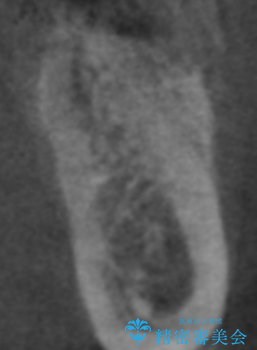

- 左下6番目の歯が欠損しており、インプラントで治療することとなりました。

骨の横幅が薄くなっており、インプラントを埋入するには骨幅が足りない状態でした。

まず最初に骨造成を行い、その後にインプラント埋入手術を行うこととなりました。

骨を増やすための手術が必要になるので、通常のインプラント治療より手術回数が一回多くなってしまうのがデメリットですが、将来的に安定したインプラントにするため、骨造成手術を前もって行いました。

しっかりとした骨幅を獲得し、理想的な太さのインプラントを埋入することができました。